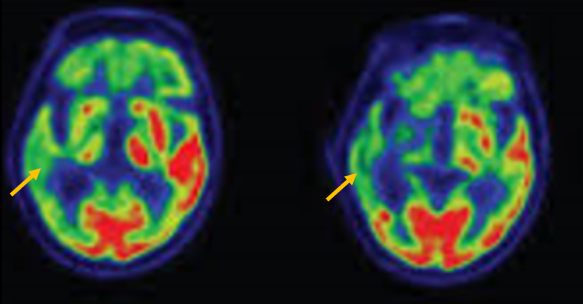

진행 핵상 마비는 대표적인 파킨슨 증후군 중의 하나입니다. 파킨슨병과 다른 점은 질병의 초기부터 중심을 잡기 어려운 체위 불안정이 나타나 자주 넘어진다는 것입니다. 파킨슨병의 경우 질병이 상당히 진행된 뒤에 체위 불안정이 나타납니다. 또한 진행 핵상 마비에서는 목 주위 근육을 비롯한 몸 중심 근육의 경축이 나타나, 목을 뒤로 젖히면서 걷는 모습이 보입니다. 그리고 눈의 운동을 조절하는 기능에 장애가 나타나 아래쪽을 바라보는 데 문제가 생겨 계단을 내려갈 때 어려움을 겪는 경우가 많습니다. 진행 핵상 마비가 의심되는 경우, 뇌 자기공명영상(MRI)에서 중뇌의 위축이 비정상적으로 심하게 나타나는 소견을 확인하거나, 뇌포도당 양전자 단층촬영(PET)에서 전두엽과 중뇌의 대사 기능이 저하된 소견을 확인하여 진단에 참고할 수 있습니다.

[진행핵상마비 환자의 뇌포도당 양전자 단층 촬영에서 확인되는 중뇌의 대사 저하 소견]